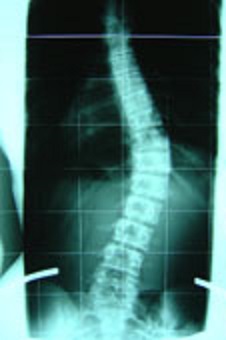

Bezüglich meines Röntgenbildes, ich habe es noch nicht eingescannt, aber ich kann euch schon mal das hier zeigen. Von der Biegung her sieht das bei mir genau so aus, ich erkenne keinen Unterschied.

- Das könnte meine Wirbelsäule sein - sieht genau so aus

- Skoliose 20 GRAD.jpg (17.06 KiB) 11479 mal betrachtet